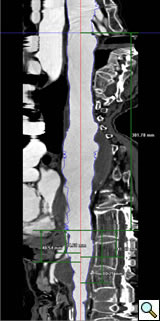

The branched TAAA stentgrafts are a modular system based on the Zenith stentgraft (Cook Inc, Bloomington, Indiana). The main body component is custom designed straight or tapered device with reinforced fenestrations or directional helical branches precisely constructed to correlate with the patients target vessels (Figure 1). Reinforced fenestrations are mated to balloon expandable covered stents (Jomed, Abbott Labs, Abbott Park, Illinois) and the directional branches are mated to self-expanding covered stents (Fluency, Bard, Inc, Tempe, Arizona).